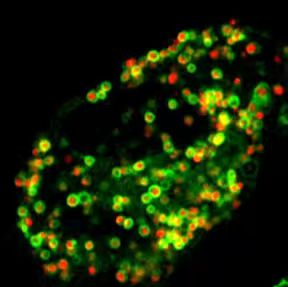

2. In Vivo Fate of Drug Delivery Systems

We systematically investigate the in vivo behavior and fate of drug delivery systems using advanced imaging and analytical tools, including intravital fluorescence microscopy, transmission electron microscopy, and synchrotron radiation-based imaging. Our studies focus on how delivery systems interact with physiological and immune barriers, such as the mononuclear phagocyte system (especially in the liver and spleen), vascular endothelium, and immune cell subsets. We analyze circulation kinetics, biodistribution profiles, cellular uptake mechanisms, and clearance pathways to elucidate the principles that govern delivery efficiency and target-site accumulation. These mechanistic insights guide the rational optimization of carrier design to improve therapeutic precision and minimize systemic toxicity.